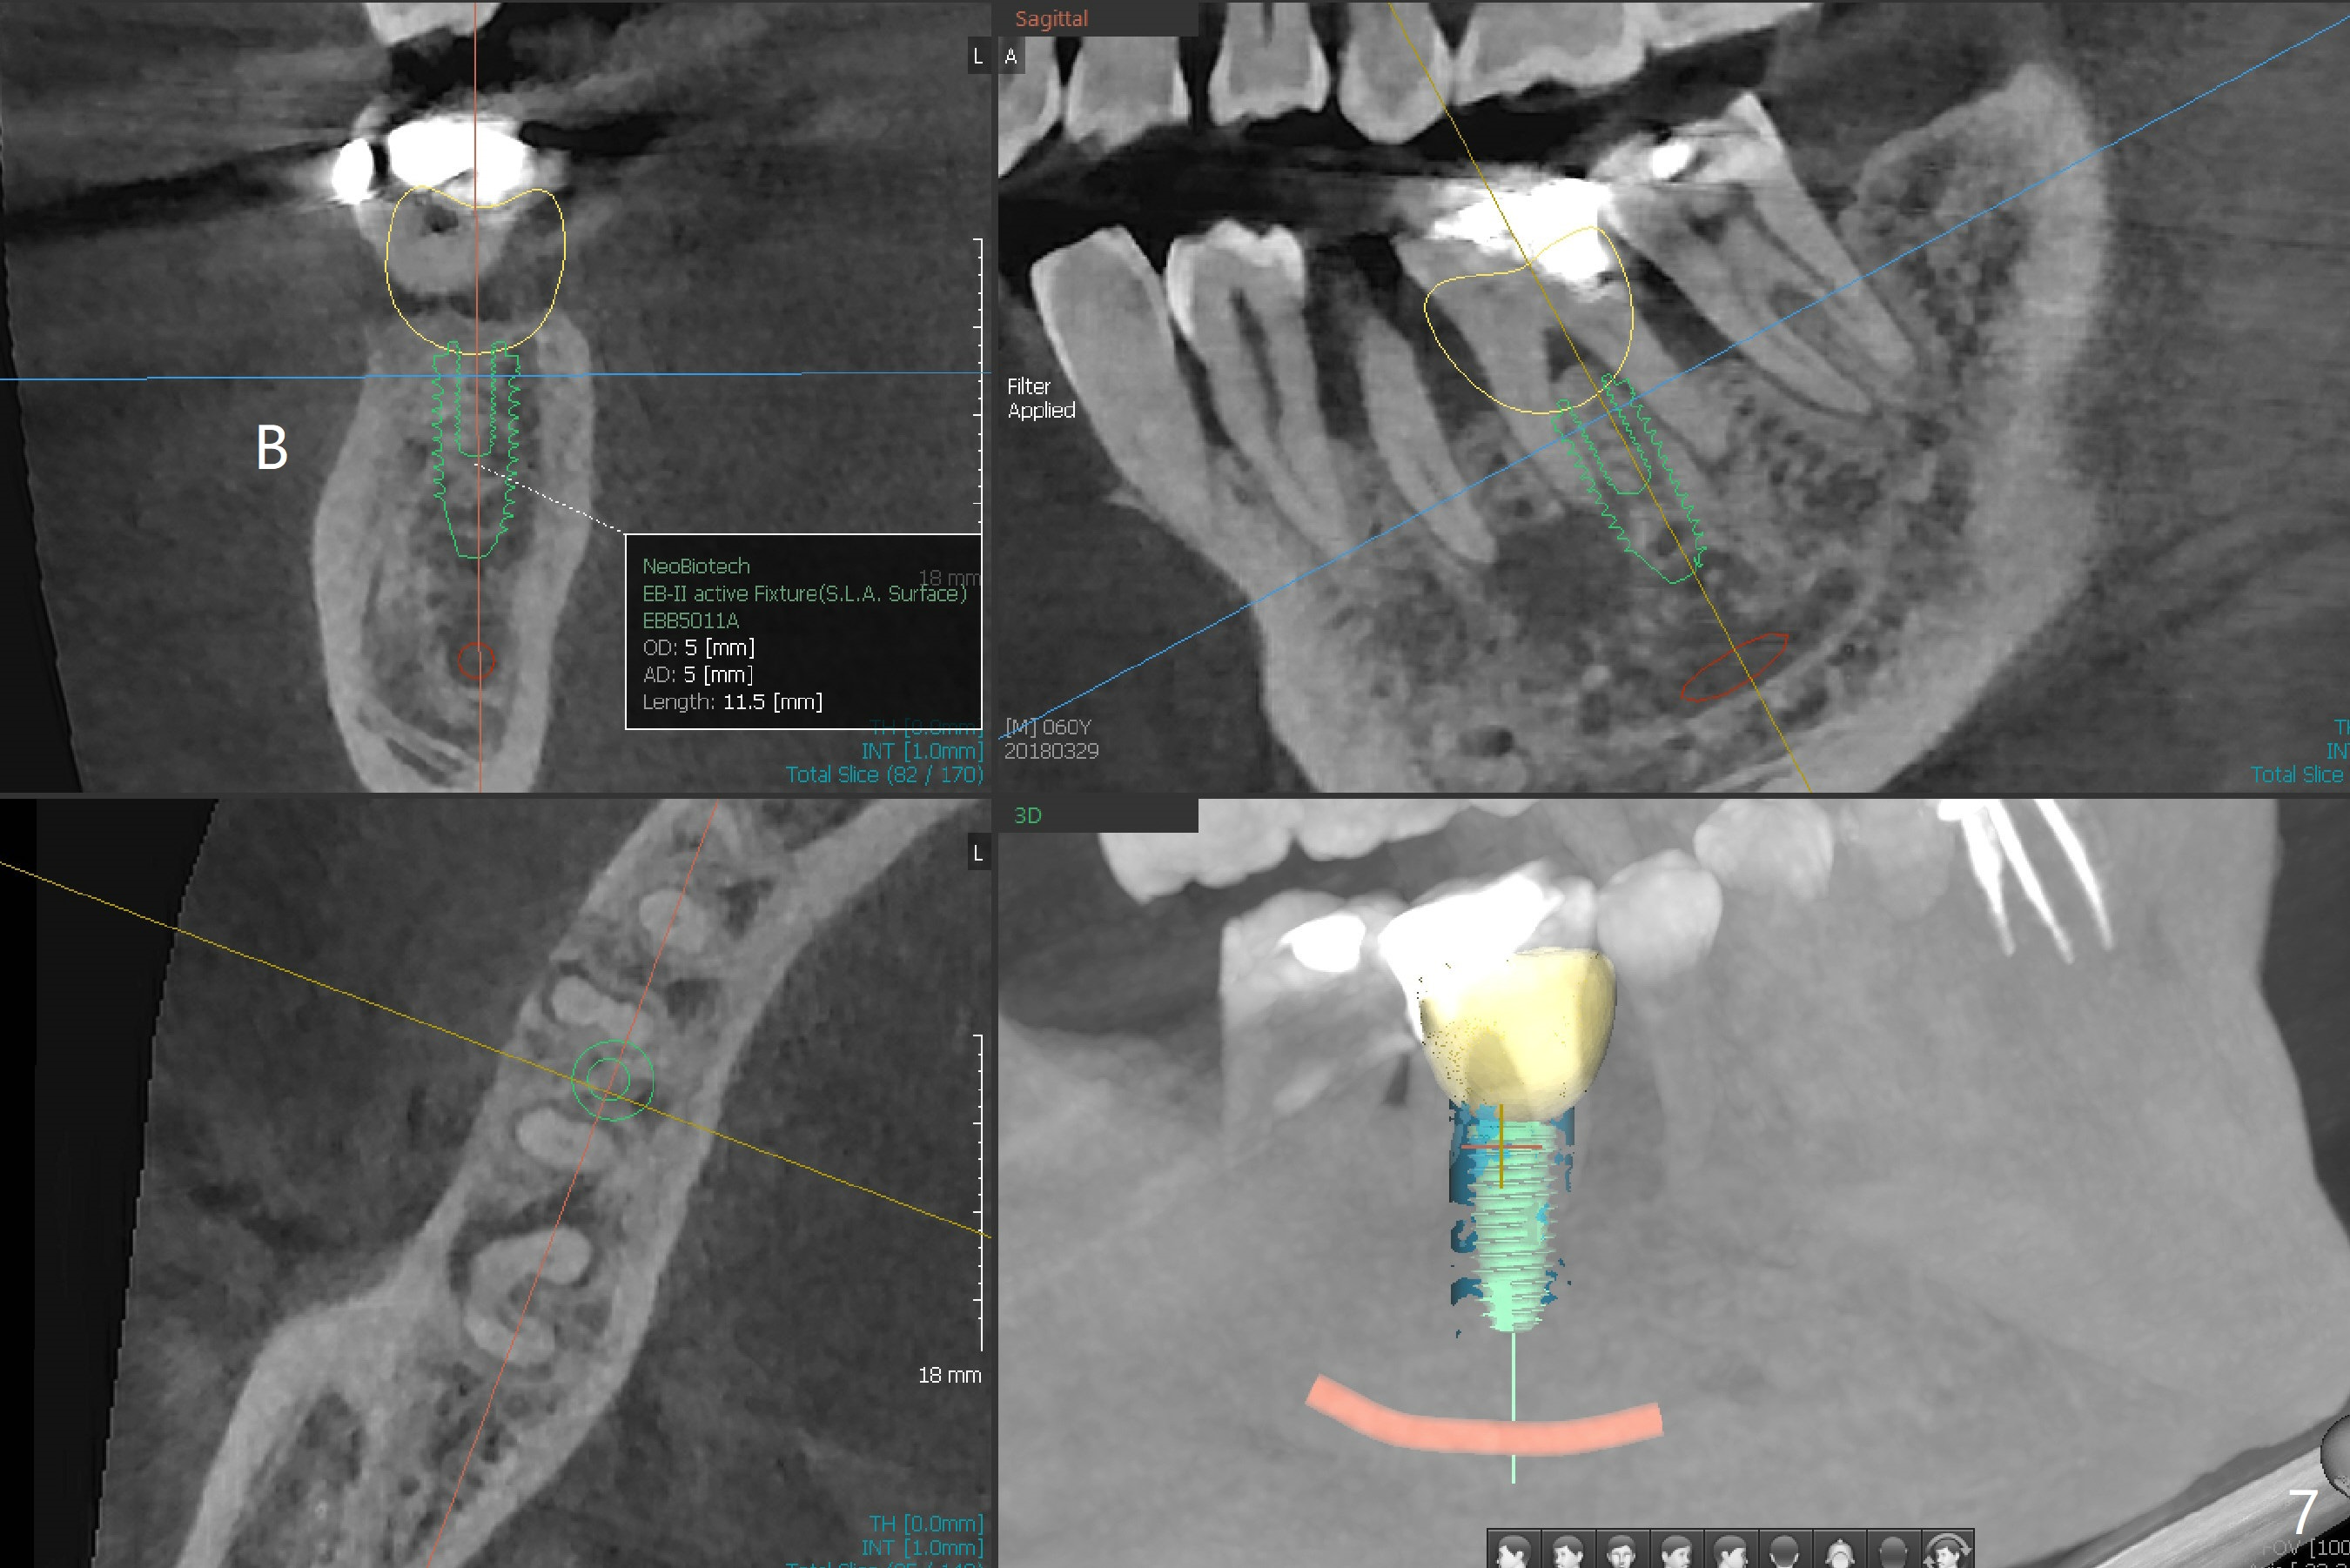

The bone seems to be wide to hold a 5x11.5 mm implant if it is placed early post extraction (Fig.7). Probably due to smoking, the socket appears to heal slow (Fig.8,9). There is mild palpation pain in the buccal vestibule. The tooth #29 remains mobile. The patient is scheduled to return for follow up in 2 months. A 5x5 cm scan is taken for the lower right posterior area for guided surgery.